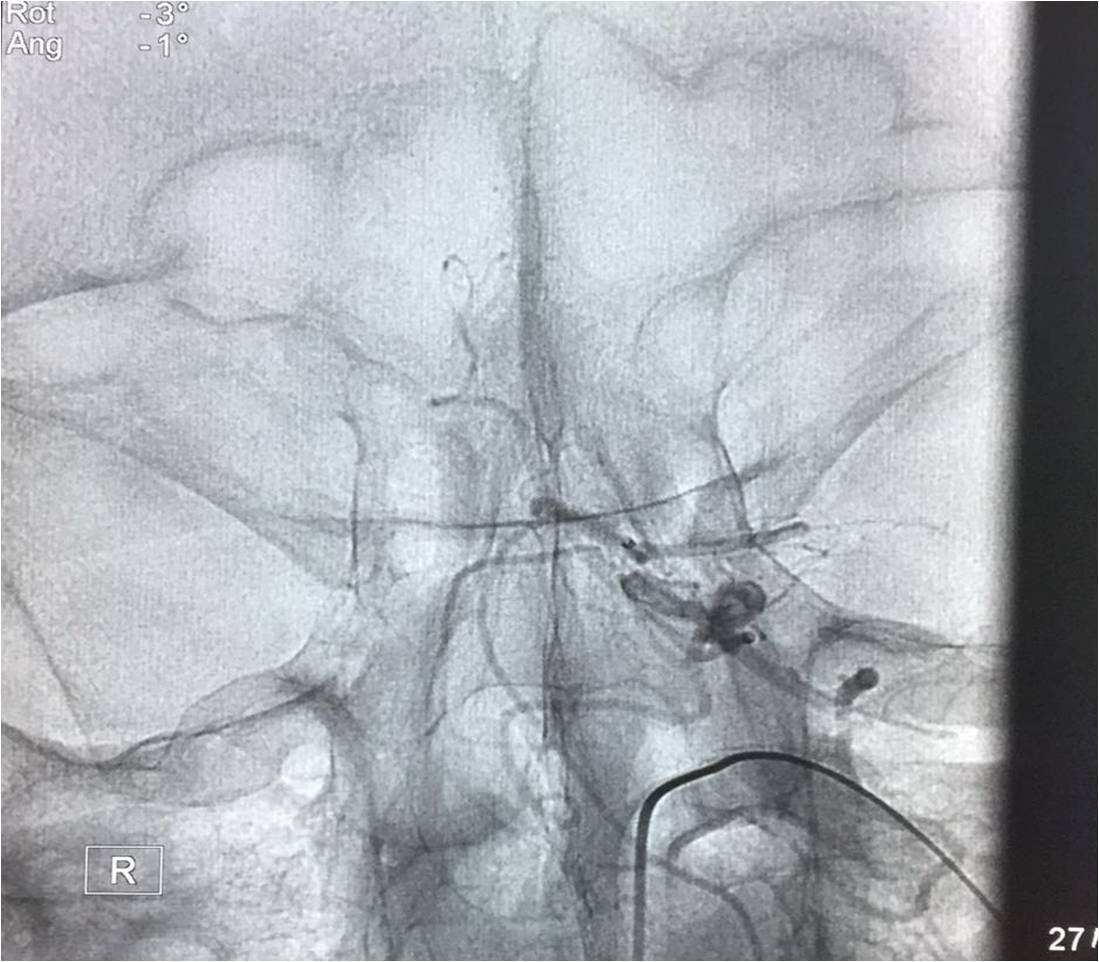

▼行造影明确动脉闭塞部位